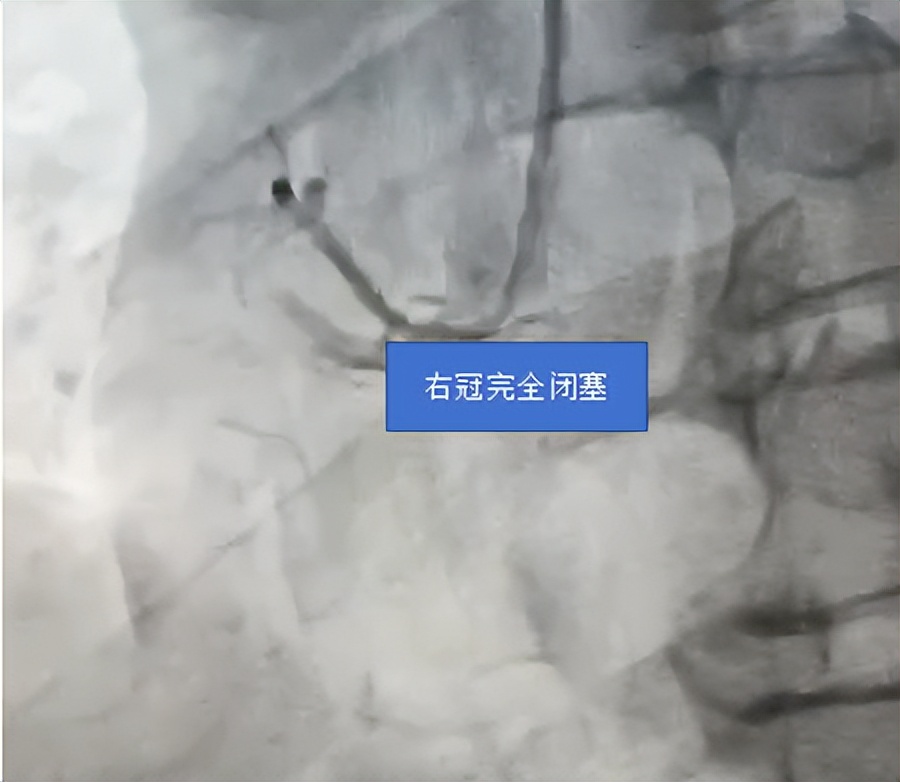

患者到达后,心血管内科介入团队迅速行动,与时间赛跑。他们争分夺秒,迎难而上,凭借精湛的医术与默契的配合, 从患者抵达医院门口到导引导丝通过闭塞血管(D - to - W 时间,国家胸痛中心要求 90 分钟以内),仅仅用了 23 分钟;球囊扩张时间(D - to - B 时间)也仅为 35 分钟。在各急救单位、部门的紧密协作下,患者的生命得以快速而有效地挽救。